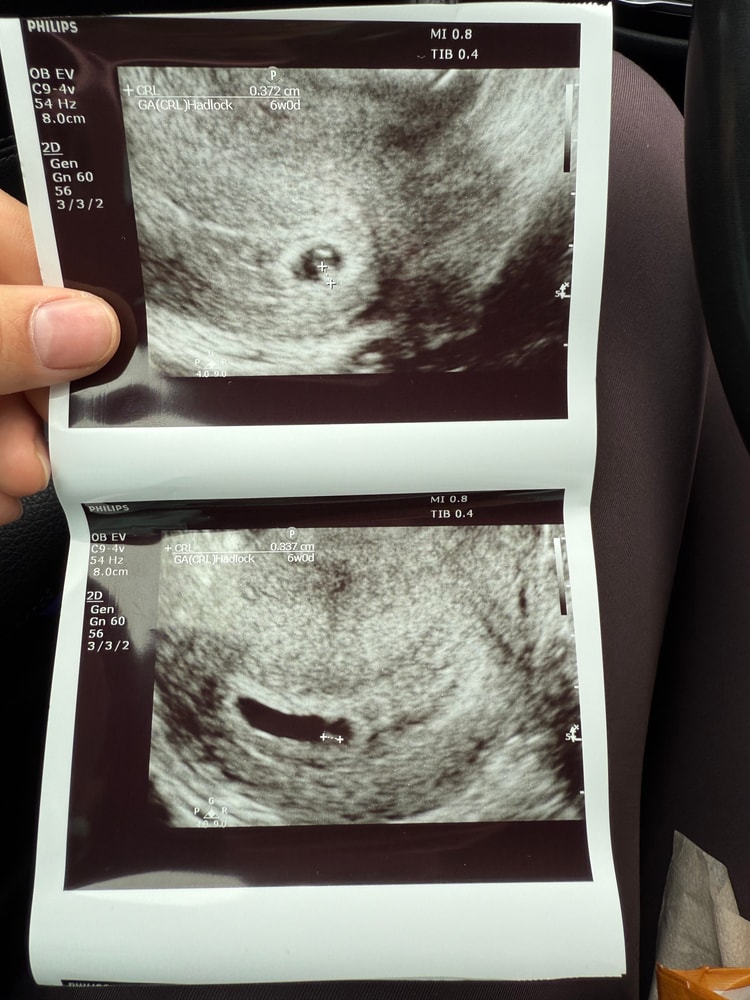

26дпп/узи

Yasmina, переносили 2🐣🐣 четырехдневные. 7дпп - 44.42 10дпп - 311.62 12дпп - 876.18 17дпп - 7618.25

Mya, Параметры эмбрионов Ваших - 0,372 и 0,337. Смотрите ктр на снимке - CRL у нас в Эстонии.